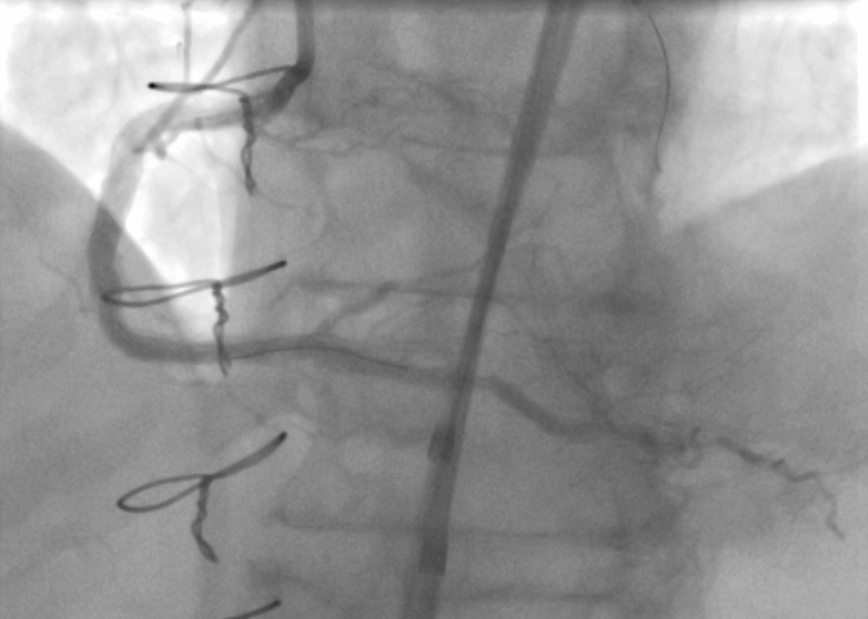

It was a great honour to participate in the international charity CTO Live Aid event with TPCH cathlab team. Post-CABG calcified RCA CTO treated with rotacut and DCB with good result for the patient.